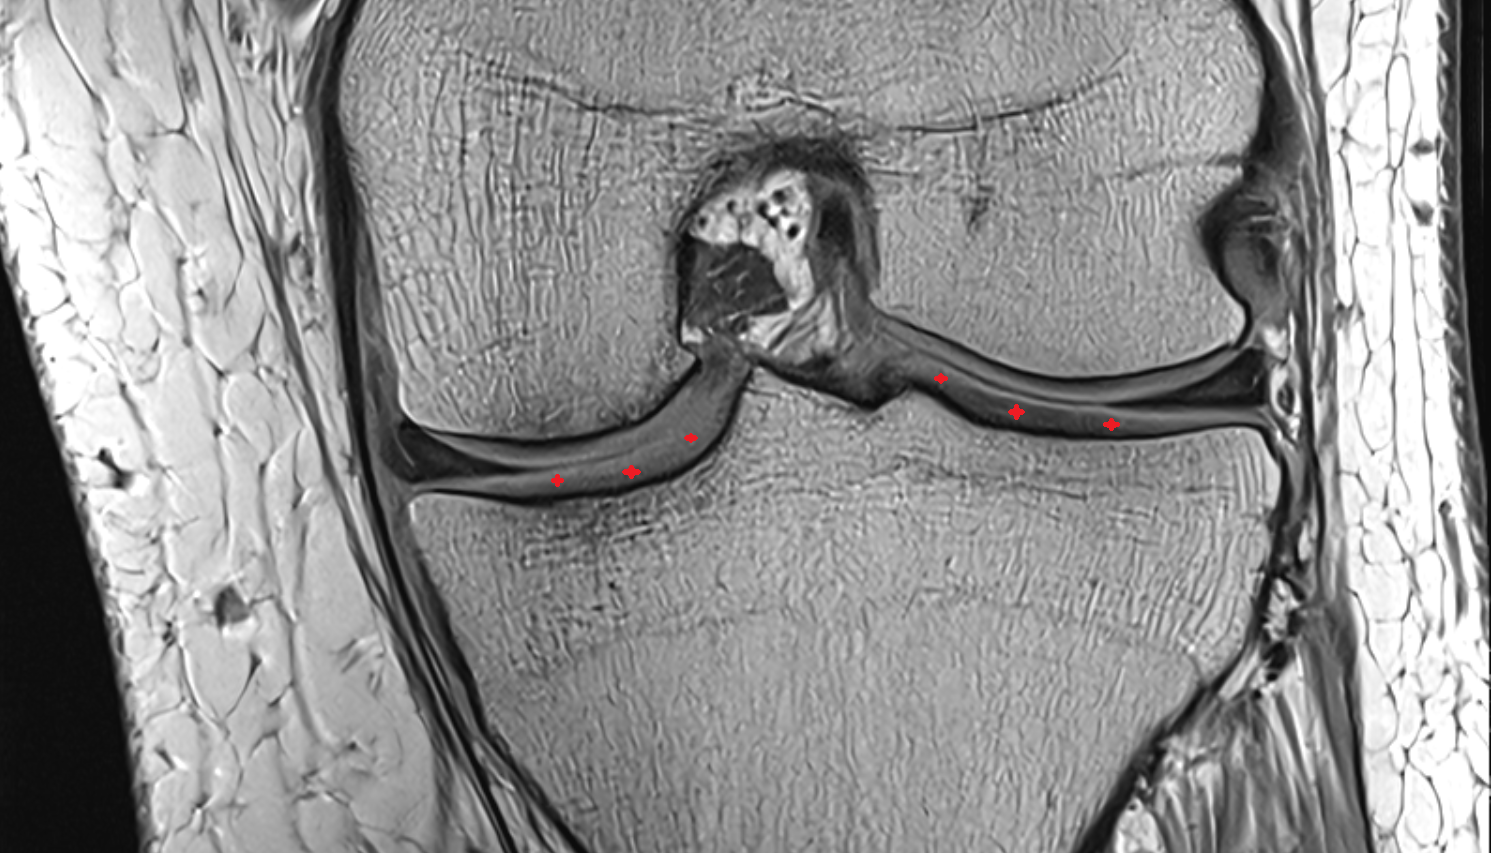

- Femoral condyle articular cartilage

- Tibial condyle articular cartilage

- Meniscus cartilage

- Medial meniscus

- Lateral meniscus

- Body of lateral meniscus

- Anterior root of lateral meniscus

- Posterior root of lateral meniscus